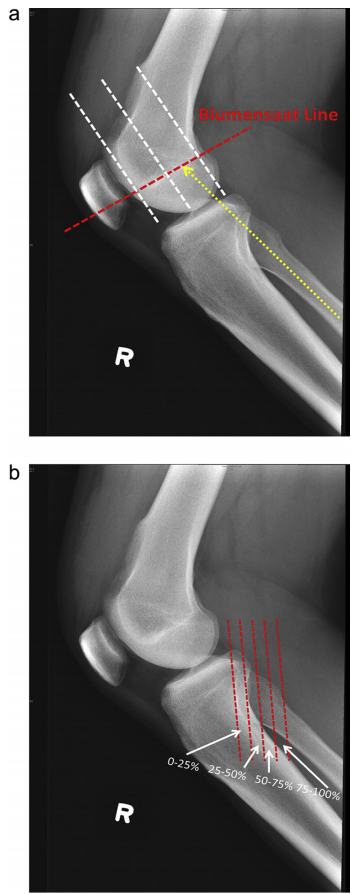

(1)blumensaat 法:患者膝关节屈曲30°时,髁间窝顶部在侧位像所显示的

2为高位髌 (1)blumensaat法:患者膝关节屈曲30°时,髁间窝顶部在侧

blumensaat法:髁间窝顶部ludloff三角底边向前做延长线正常髌骨下极

line)在侧位图像上可清晰显示,以blumensaat线与股骨外侧髁前后缘交点